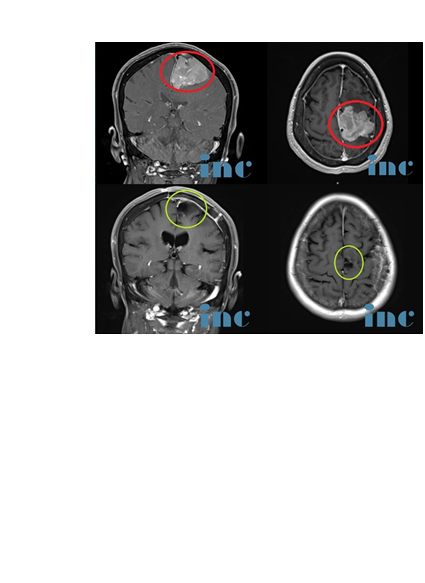

INC国际神经外科医生集团脑膜瘤手术治疗案例一则